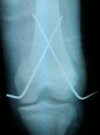

Results: Three cases had open book pelvic injuries and one of them also had a vaginal tear. All of the open book injuries occurred after the patron's thighs violently abducted despite adhering to the recommended starting position that suggested patrons cross their legs. The fourth case was of a 25-year-old man who sustained a posterior shoulder dislocation as a result of his arms flailing despite attempting to adhere to the rule recommending that the patron place his arms across his chest. The final case was of a 14-year-old boy who was involved in an atypical collision injury, resulting in the boy sustaining a displaced distal femoral fracture.